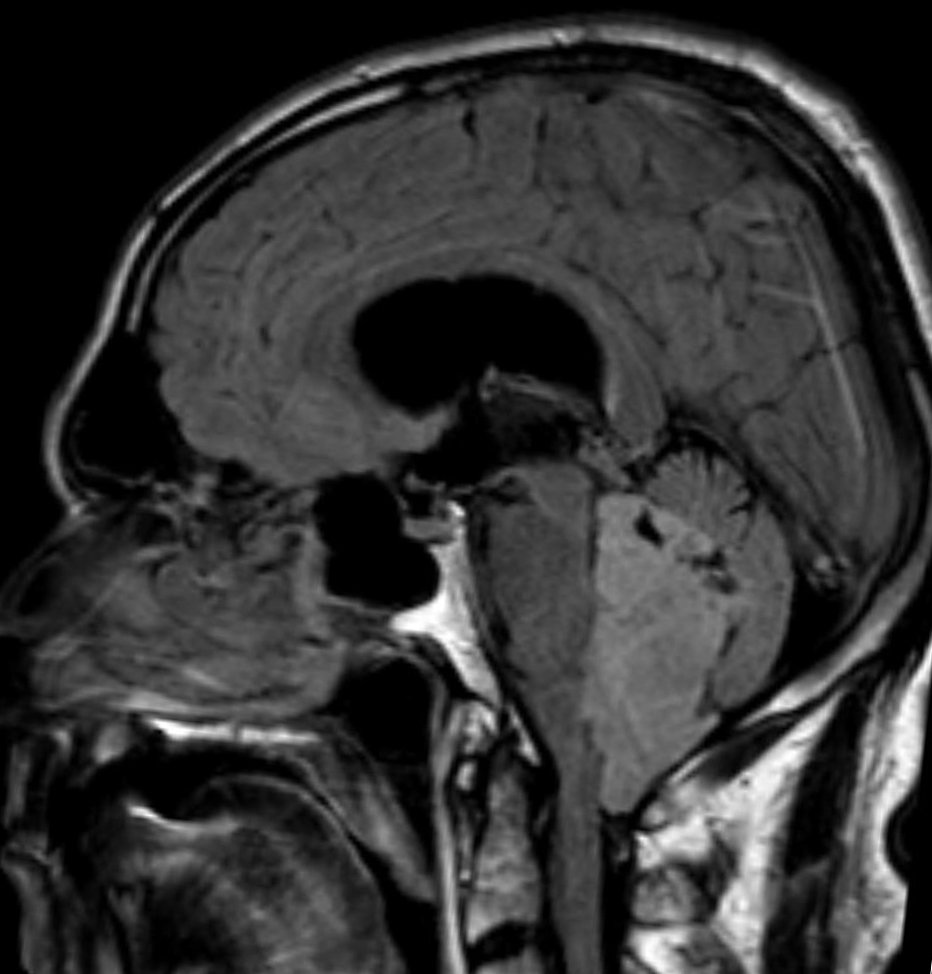

Axial T2Sagital FLAIR

Axial T1Axial T1 GadAxial T1 Gad/fat sat

For a detailed discussion of ependymoma imaging see Radiopedia for an excellent discussion on ependymoma imaging by Weerikoddy and Galliard.

MRI Brain

Careful examination of the entire neuraxis is required to assess for the presence of CSF seeding.